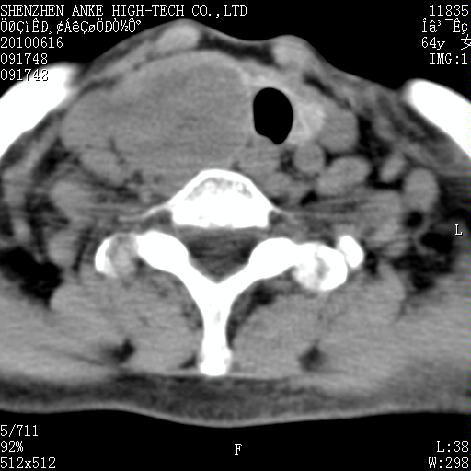

标题: CT27132:患者女,64岁,颈部及全身多处包块,现觉吞咽困难4 [打印本页]

标题: CT27132:患者女,64岁,颈部及全身多处包块,现觉吞咽困难4

右侧甲状腺占位,肿瘤可能性大,癌

右侧甲状腺癌伴右颌下腺淋巴结转移

右侧甲状腺癌伴淋巴结转移

右侧甲状腺癌伴淋巴结转移可能性大

右侧甲状腺癌伴淋巴结转移可能性大。

右侧甲状腺癌伴右颌下腺淋巴结转移!建议增强!